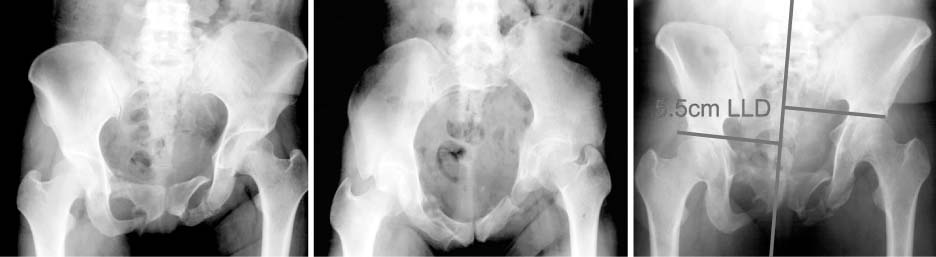

Fig. 2

Radiographs show posterior translation of the left hemipelvis on anteroposterior and inlet view and 5.5 cm significant superior migration of the left hemipelvis on outlet view. LLD: limb length discrepancy.

Fig. 2 Radiographs show posterior translation of the left hemipelvis on anteroposterior and inlet view and 5.5 cm significant superior migration of the left hemipelvis on outlet view. LLD: limb length discrepancy.